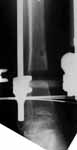

Briefly 22 yo male rollover MVA 1 yr ago. Isolated lower extremity injury. 3b open distal 1/3 femur and proximal 1/3 tib/fib (ipsilateral). Lots of debris dirt grass clothes and carpet. Treated emergently with debridement and spanning frame.

Injury Films

femur

lateral

tibia